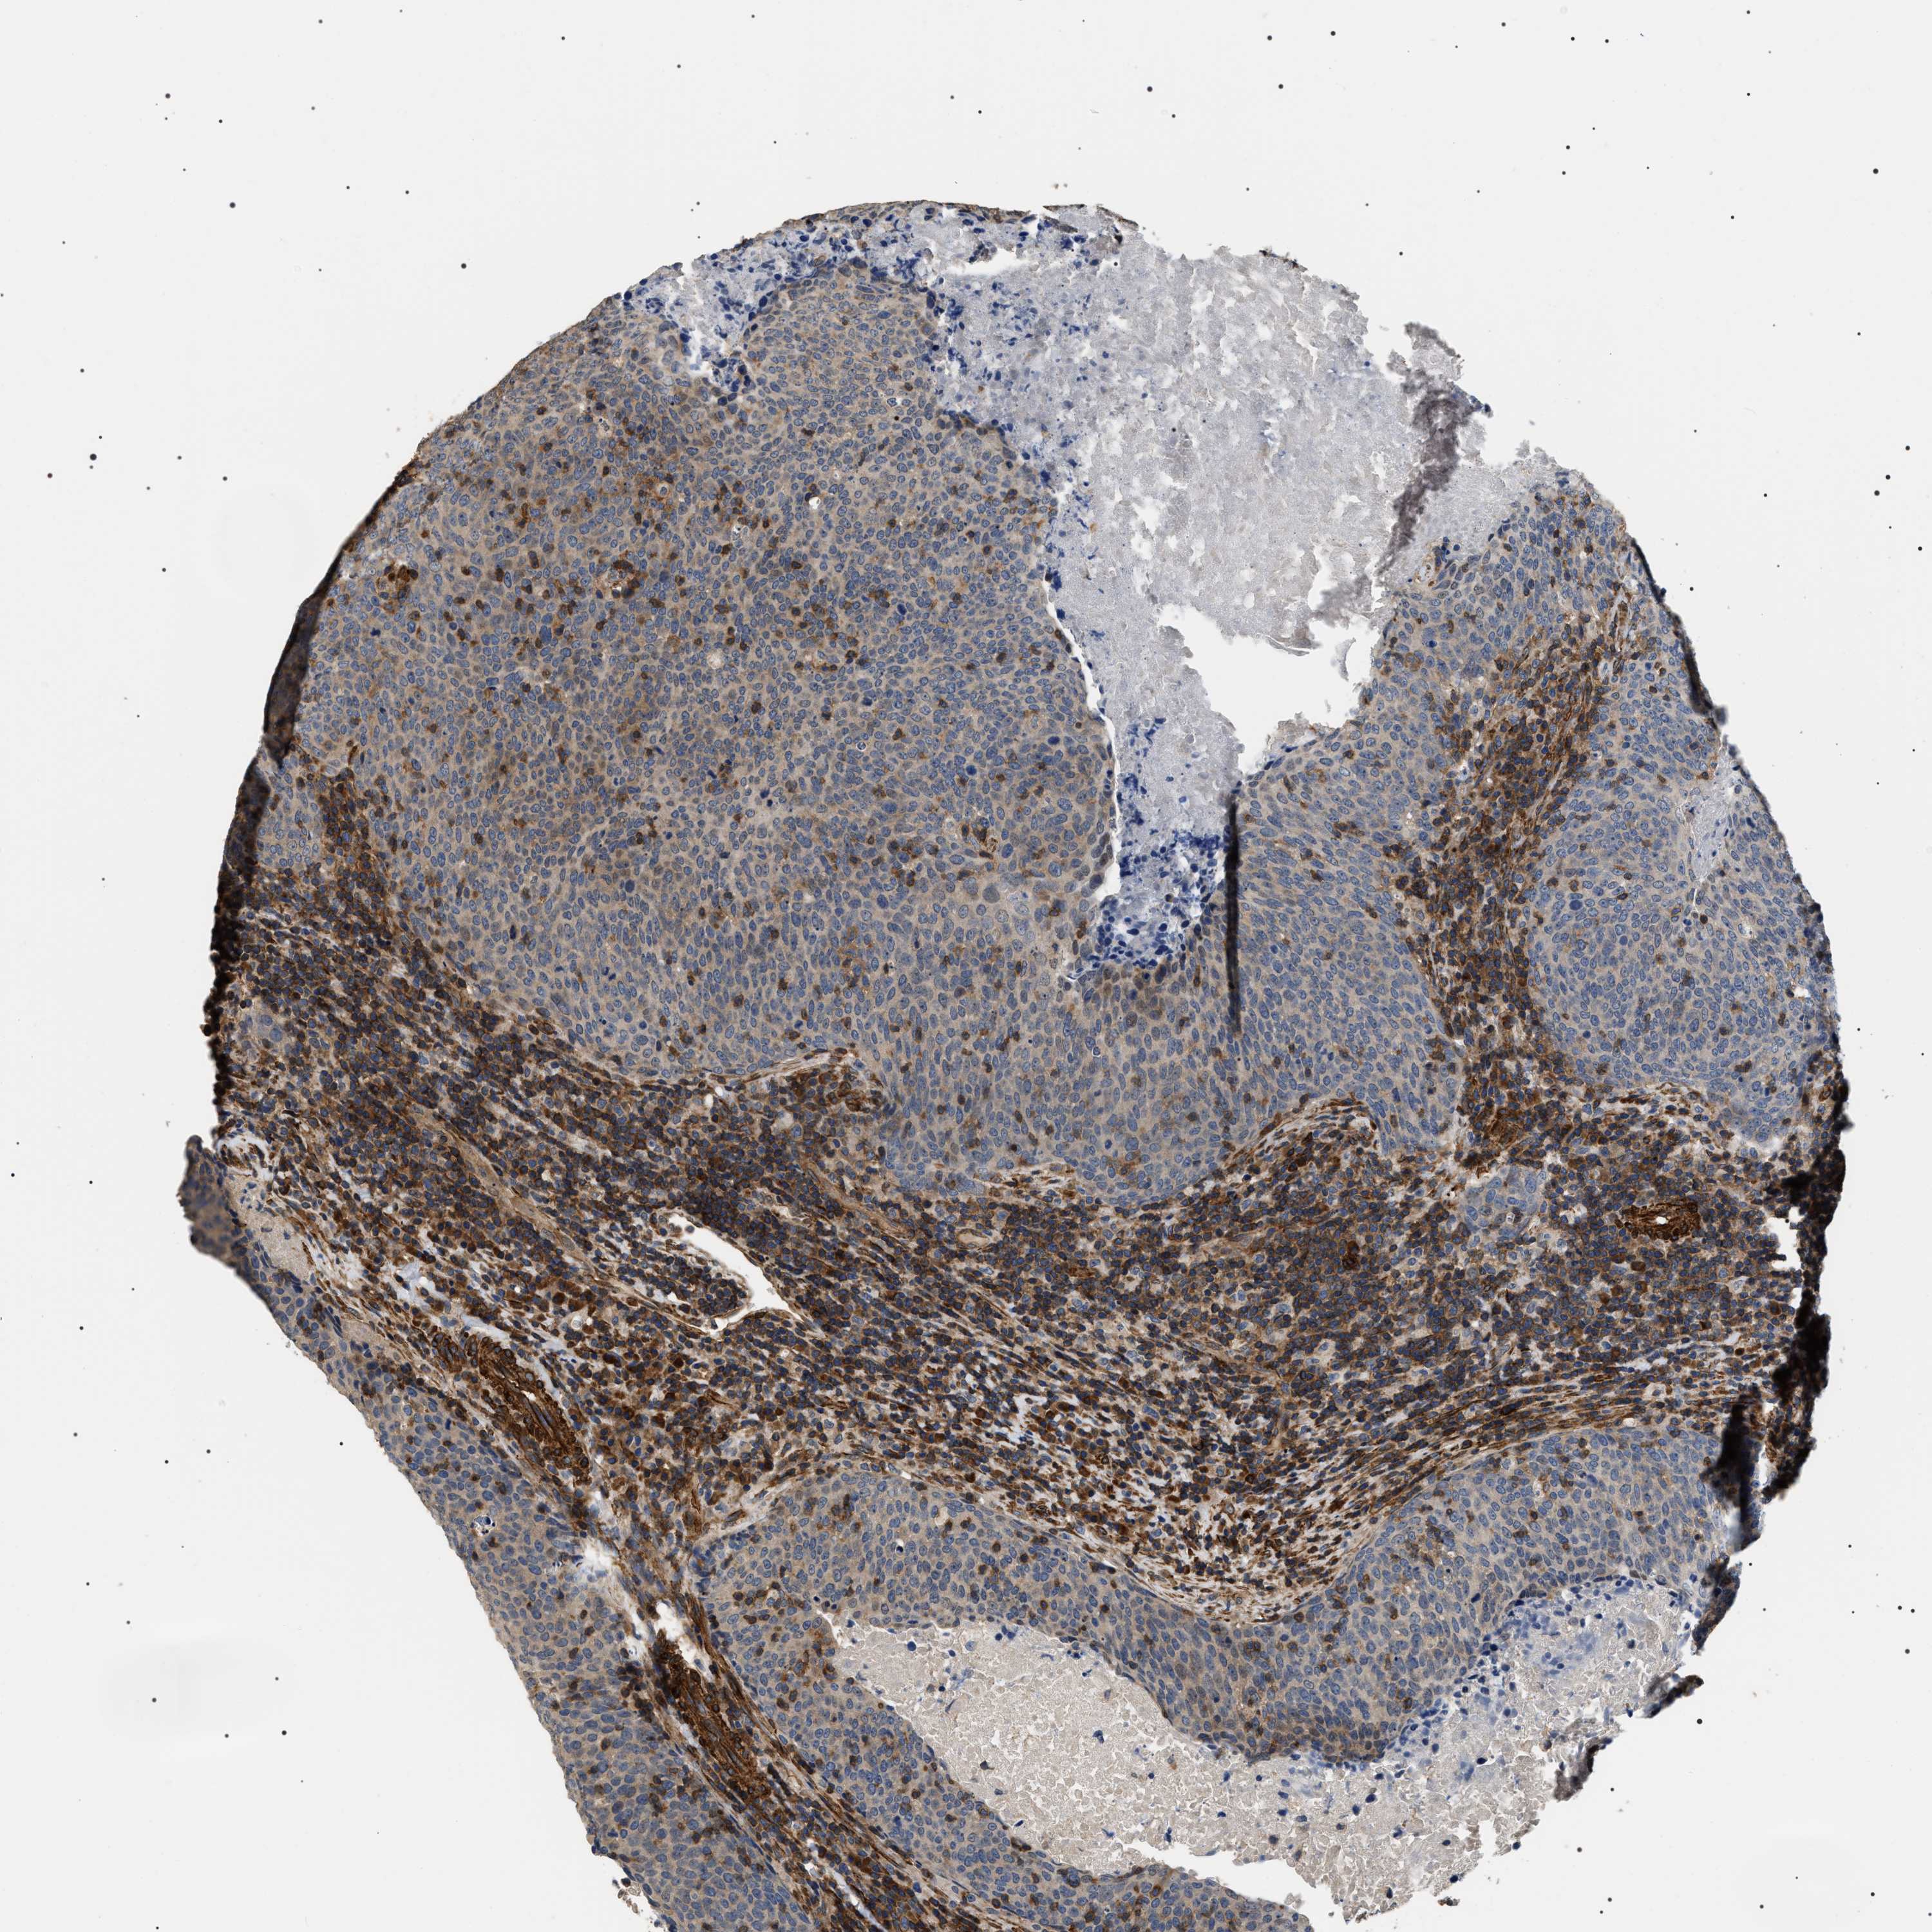

HEAD AND NECK CANCER - Protein expressioni

A mouse-over function shows sample information and annotation data. Click on an image to view it in a full screen mode. Samples can be filtered based on level of antibody staining by selecting one or several of the following categories: high, medium, low and not detected. The assay and annotation is described here.

Antibody stainingi

Antibody staining in the annotated cell types in the current human tissue is reported as not detected, low, medium, or high, based on conventional immunohistochemistry profiling in selected tissues. This score is based on the combination of the staining intensity and fraction of stained cells.

Each image is clickable and will lead to virtual microscopy that enables deeper exploration of all samples and also displays staining intensity scores, fraction scores and subcellular localization as well as patient and tissue information for each sample.

Antibody HPA020386

Staining

High

Medium

Low

Not detected

Intensity

Strong

Moderate

Weak

Negative

Quantity

>75%

75%-25%

<25%

None

Location

Nuclear

Cytoplasmic/membranous

Cytoplasmic/membranous,nuclear

Squamous cell carcinoma, NOS